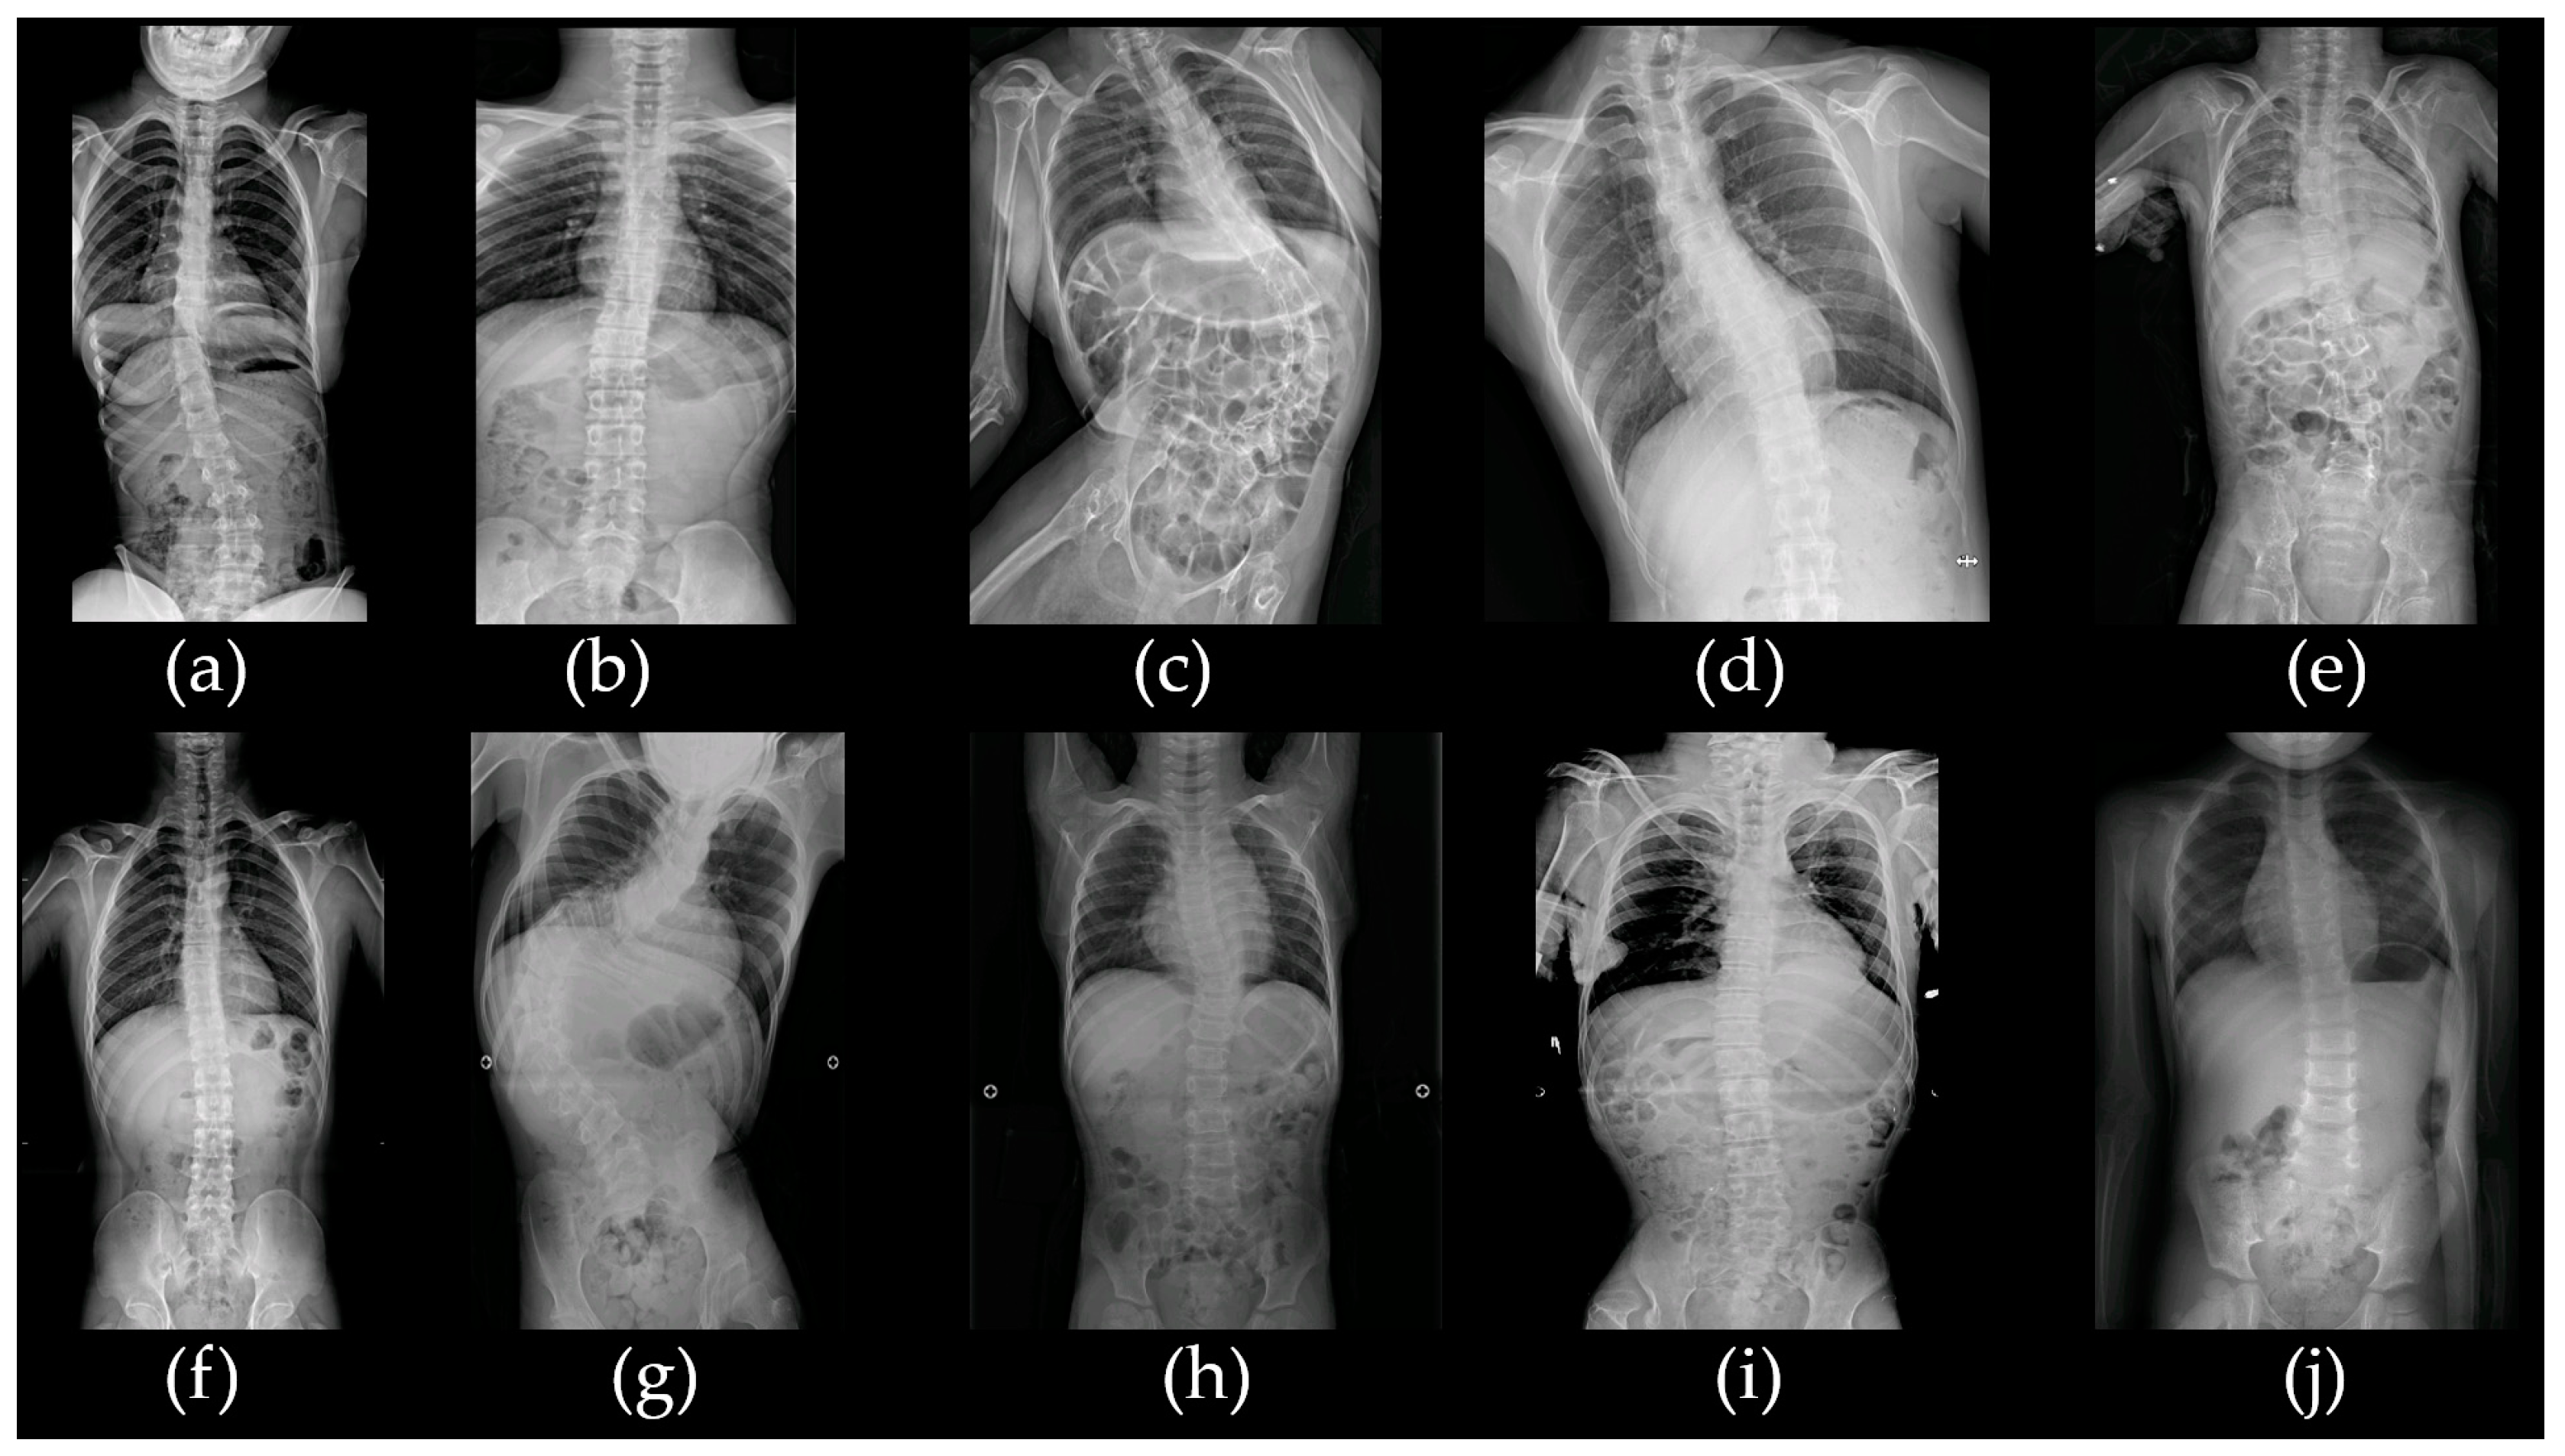

2.1.1. Patient acp01k with SLC2A1 c.277C>T/p.Arg93Trp Variant

2.1.2. Patient acp02s with 15p11.2 Microdeletion

2.1.3. Patient acp03k with Bi-Allelic PLAA c.1039+1G>A and c.1834C>T/p.Pro612Ser Variants

2.1.4. Patient acp05y with CDC42BPB c.4049G>A/p.Arg1350Gln Variant

2.1.5. Patient acp06l with 17p11.2 Duplication

2.1.6. Patient acp07l with CACNA1D c.1846T>C/p.Cys616Arg Variant

2.1.7. Patient acp08p with Bi-Allelic ALG12 c.437G>A/p.Arg146Gln and c.788A>G/p.Tyr263Cys Variants

2.1.8. Patient acp09k with 12p13.33p11.23 Duplication and 18p11.32 Microdeletion

2.1.9. Patient acp10k with Bi-Allelic SACS c.11101T>C/p.Trp3701Arg and c.12973C>T/p.Arg4325Ter Variants